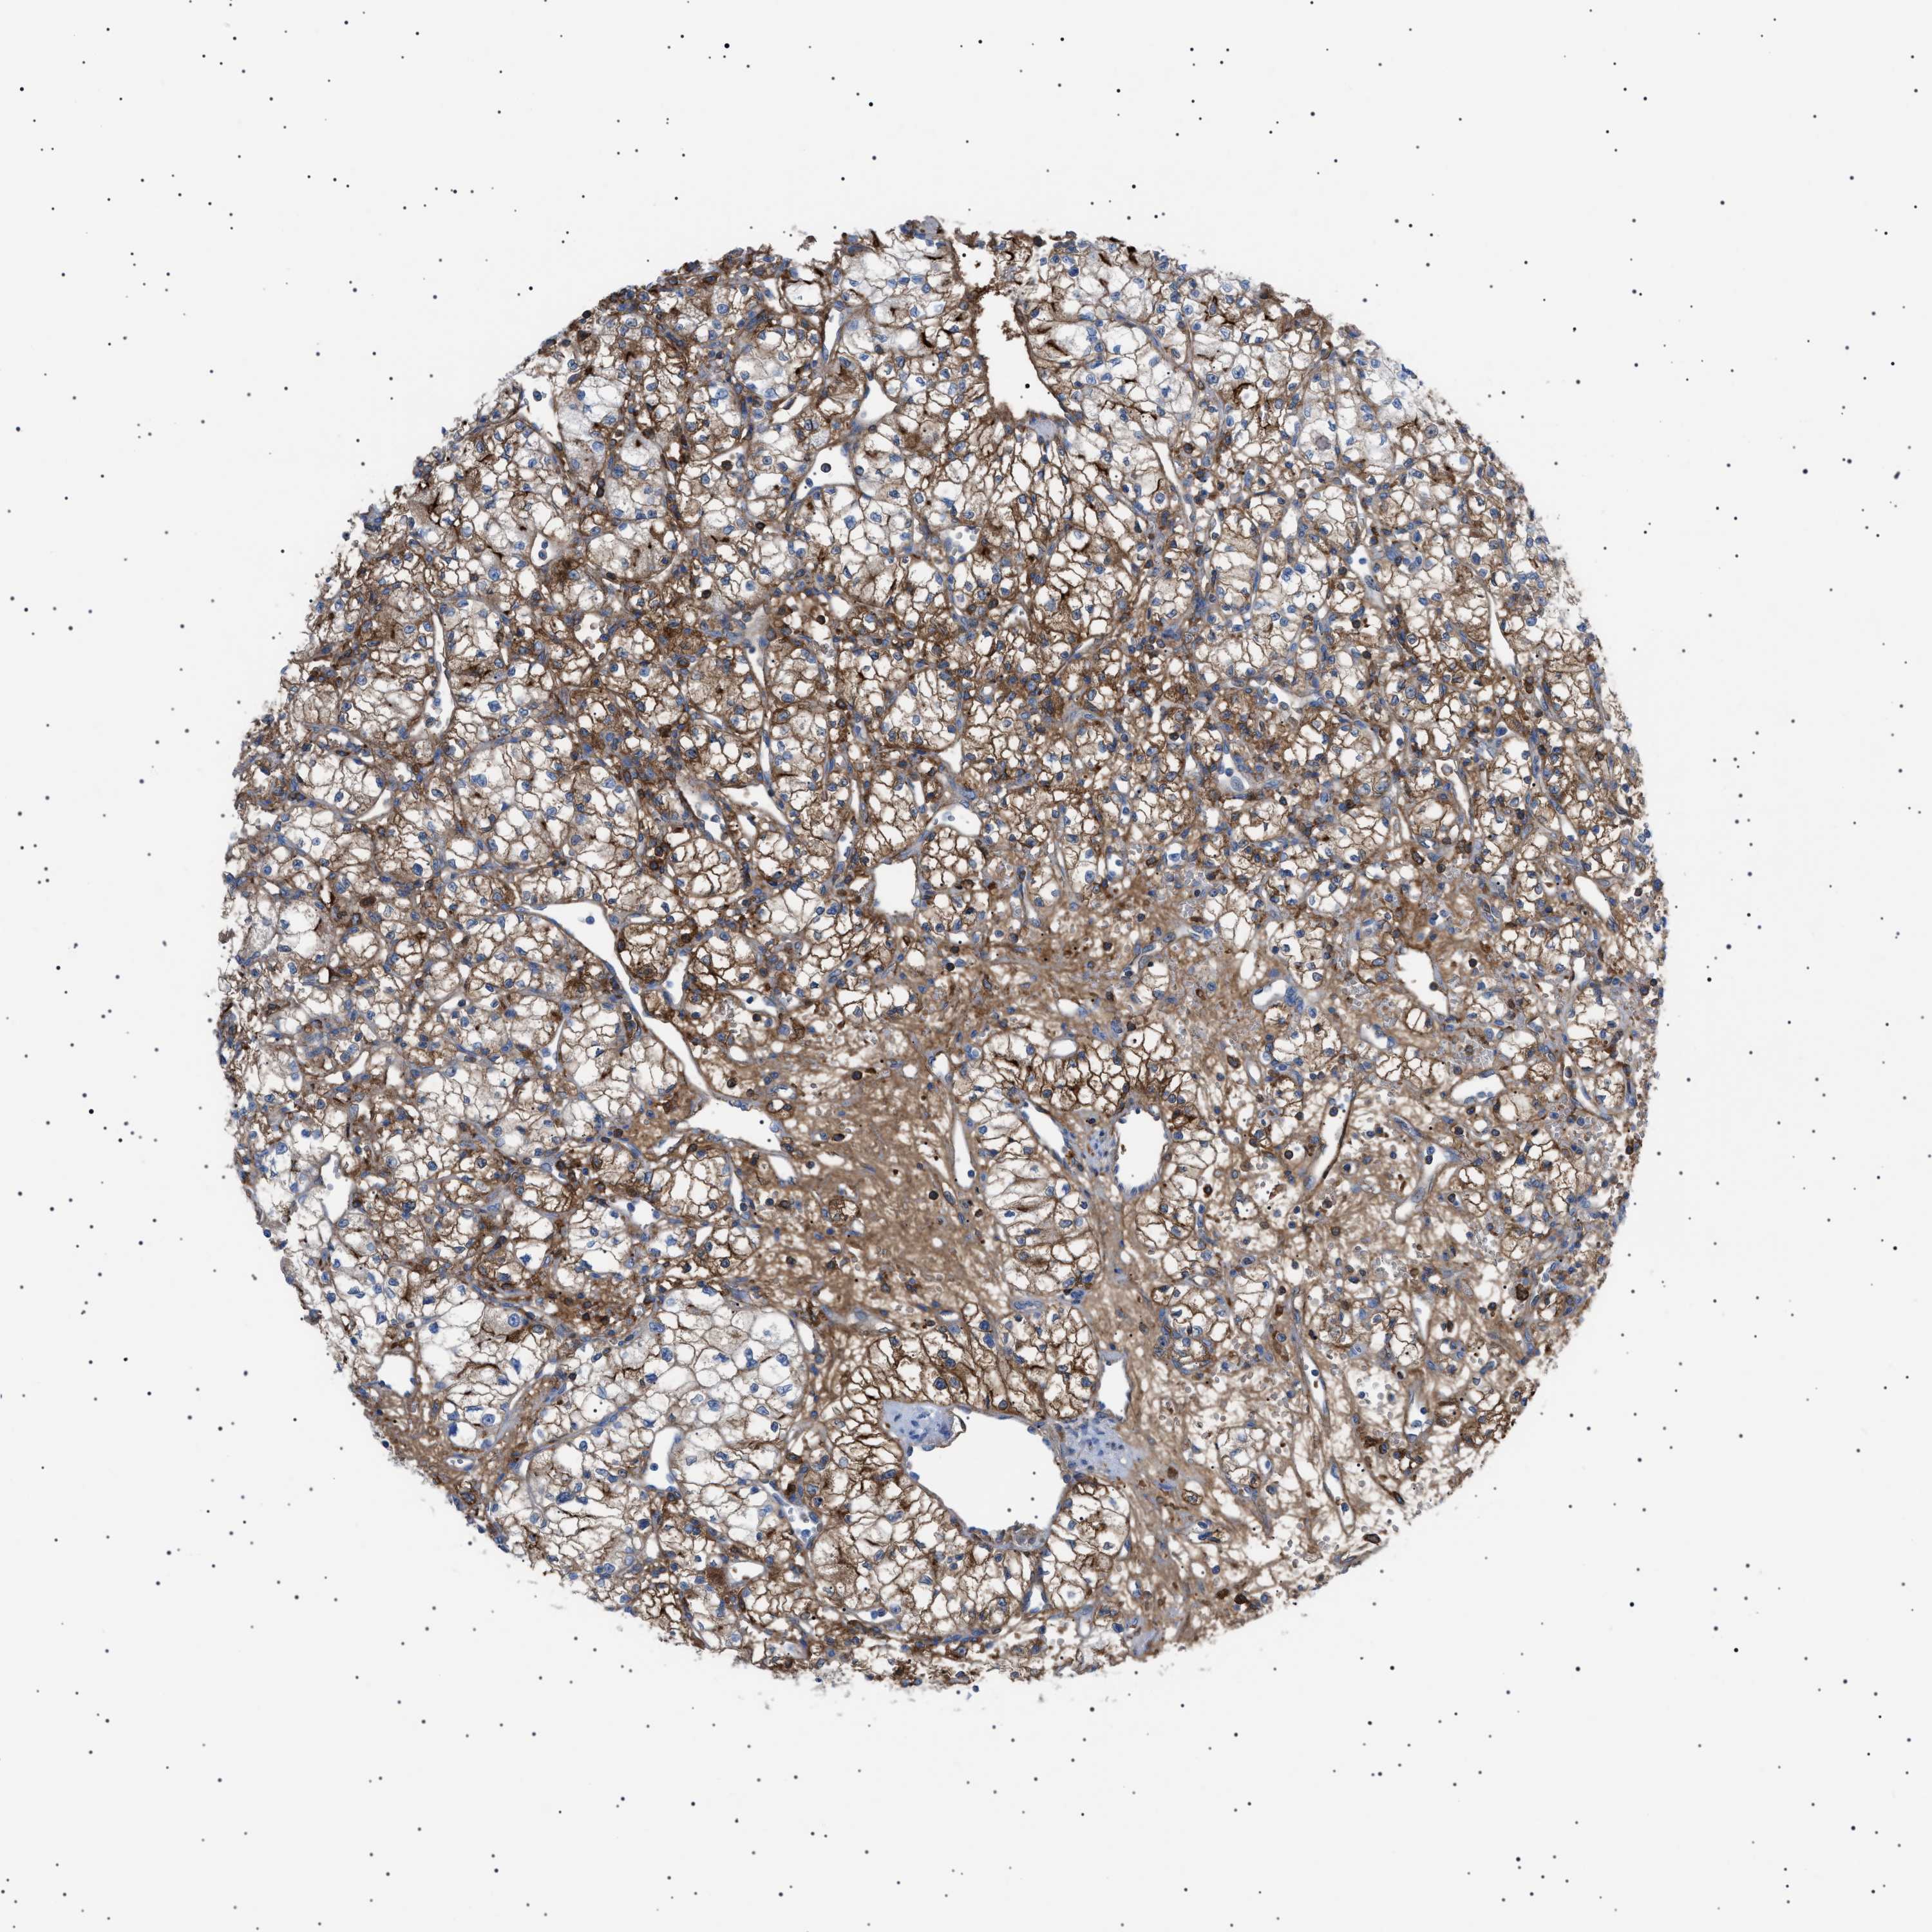

CANCER RENAL CANCER Show tissue menu

KICH TCGA KIRC TCGA KIRC VALIDATION KIRP TCGA PROTEIN RCC CPTAC PROTEIN EXPRESSION